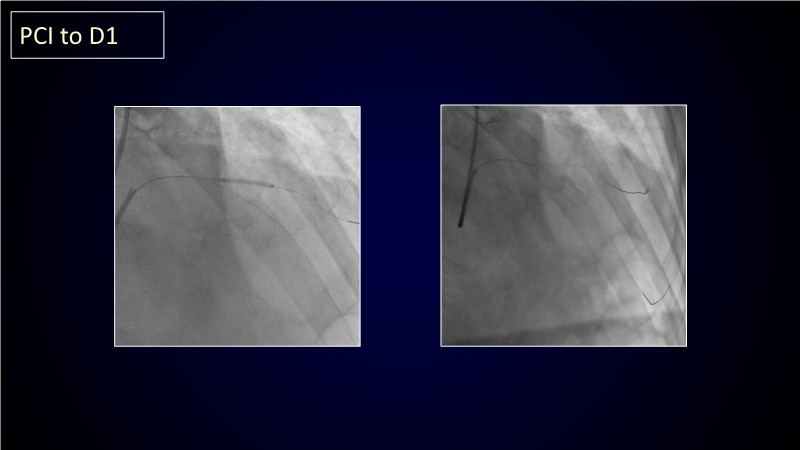

Calcified coronary lesions are a major challenge in PCI. This PCRGulf-GIM 2025 session showcases a complex case with intravascular imaging, highlighting how IVUS 123 guides each step.

From planning the procedure and understanding calcium distribution, to lesion preparation with modern modification tools, and post-PCI assessment to confirm stent expansion and detect complications, this session demonstrates practical, imaging-driven strategies.